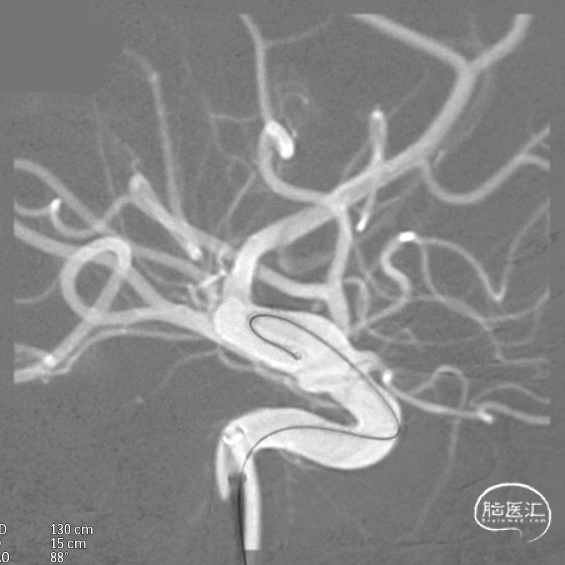

输送导丝及微导管回撤:释放至支架末端,减张系统,回撤支架导管,释放支架。沿支架推送杆,调节系统张力,将支架导管通过支架到达C7段。

支架内使用成襻微导丝进行按摩,使支架充分贴壁。

术后造影:支架覆盖两枚动脉瘤瘤颈,贴壁良好,瘤体内可见造影剂滞留。

术后支架显影: